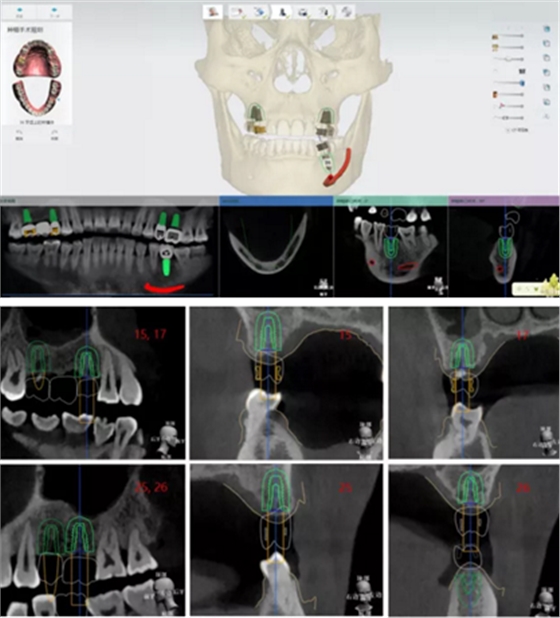

手術(shù)方案規(guī)劃

手術(shù)規(guī)劃設(shè)計

設(shè)計植入5顆種植體

查看種植體螺絲通道穿出虛擬修復體的位置。

查看種植體在牙槽嵴頂穿出位置。